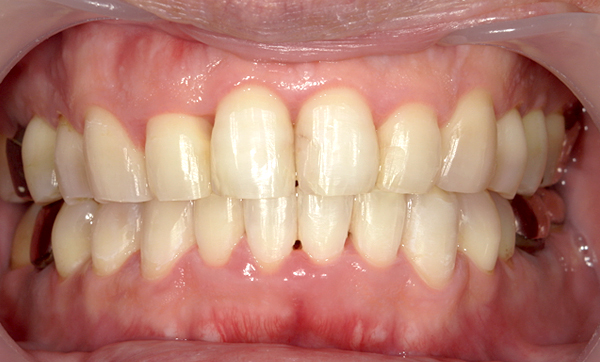

症例_007 「上下の前歯」症例

治療期間:11ヶ月金額:54万円+税40代女性捻転歯

Before | After |